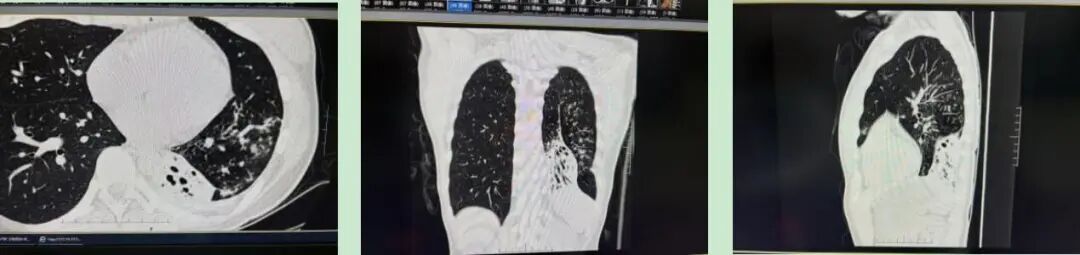

呼吸介入团队分阶段为小林实施精准介入治疗,经过一个半月三次介入治疗,小林左肺功能显著恢复,呼吸顺畅了,体重也增加了6斤,为后续康复奠定坚实基础,也为她未来的生活质量提供有力保障。

手术后影像图像示:肺组织含气量增加,痰栓减少,部分肺组织重新复张